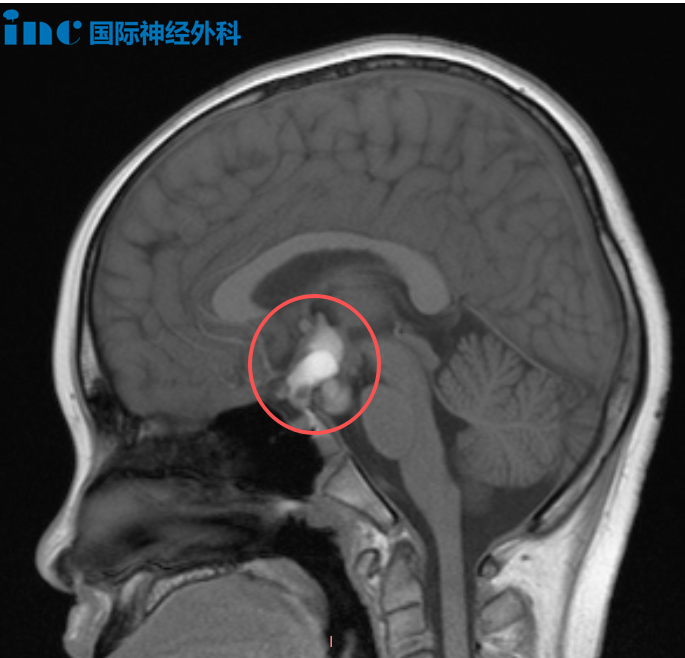

12岁男孩涛涛今年8月因头痛查出颅咽管瘤,20mm×15mm×27mm大小的病变已经让脑干受压后移,压迫到视交叉后方的视路系统。

颅咽管瘤手术首要目标是安全、彻底地到达并切除肿瘤;其次,要尽可能保留垂体柄。垂体柄是连接大脑下丘脑与垂体腺之间的重要通道,垂体腺负责分泌激素,而下丘脑则像汽车的刹车和油门,负责调控激素分泌的节奏,例如早晨皮质醇的分泌量高于下午,这种精细的调节正是下丘脑的功能,因此垂体柄的完整性非常重要。第三个目标是在不损伤视神经等关键结构的前提下,尽量实现肿瘤的全切除,以防止术后复发。如果能够在保护垂体柄和视神经的同时实现完全切除,那将是理想的手术结果。

今天的面对面交流中,巴教授再次强调,手术将在尽可能全切肿瘤的同时保留垂体柄。就患儿目前的肿瘤尺寸来看,实现全切并保留垂体柄的可能性较大;若肿瘤继续增大,手术难度与风险也将随之增加。巴教授也关注到患儿术前的激素水平整体尚可,仅早晨皮质醇值略偏低。面对患儿父母对孩子寿命的深切担忧,他表示:“颅咽管瘤不是恶性肿瘤,不会影响孩子的正常寿命。”